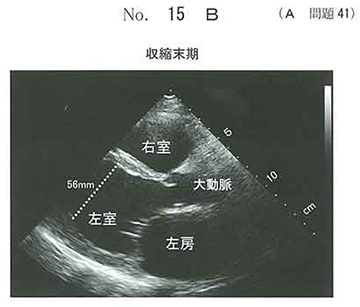

急性左心不全を伴うDCM。